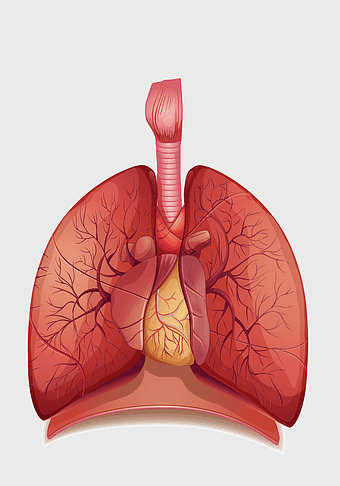

Pulmonary edema symptoms, chronic obstructive pulmonary disease diagram, kidney failure effects on lungs, pulmonary circulation illustration, lung disease diagnostic, respiratory health visuals, human anatomy respiratory system, PNG

- pulmonary edema symptoms

- chronic obstructive pulmonary disease diagram

- kidney failure effects on lungs

- pulmonary circulation illustration

- lung disease diagnostic

- respiratory health visuals

- human anatomy respiratory system